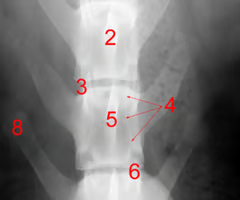

Identify structure 1:

Spinous process

Identify structure 2 and 4:

Vertebral canal

Pedicle

Identify structure 3:

Intervertebral foramen

Identify structure 5:

Vertebral body

Identify structure 6:

Articular process

Identify structure 7:

Dorsal laminae

Identify structure 8:

Transverse process